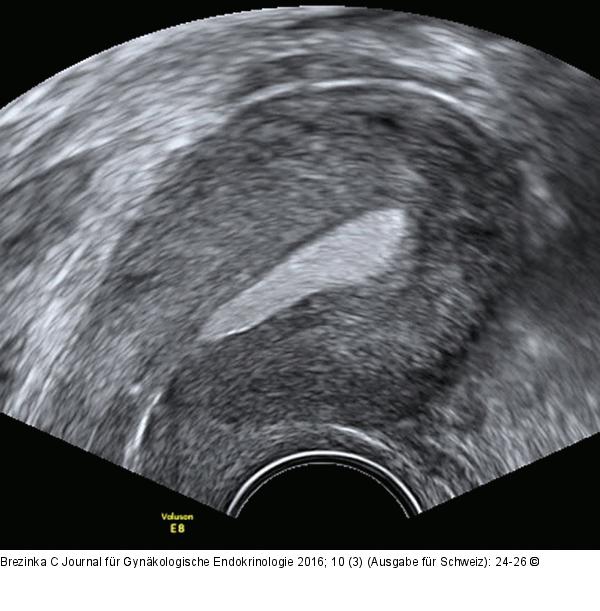

Abbildung 7: Ultraschall-Serometra Selber Fall und selbe Einstellung wie Abbildungen 5 und 6: Mit echodensem Kontrastmittel wie z. B. Sonovue® kann man Schleimhautpolypen deutlich weniger gut darstellen als mit NaCl. |

Abbildung 7: Ultraschall-Serometra

Selber Fall und selbe Einstellung wie Abbildungen 5 und 6: Mit echodensem Kontrastmittel wie z. B. Sonovue® kann man Schleimhautpolypen deutlich weniger gut darstellen als mit NaCl. |